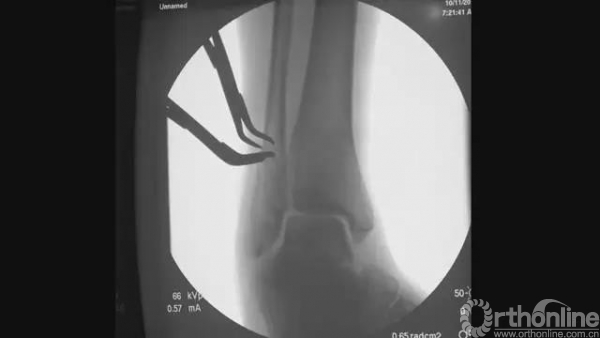

远端切一个小口,行髓内钉导针植入

透视下将导针置于腓骨髓腔内

正侧位透视满意,均位于中心